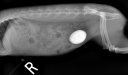

• Ils ont mangé quoi ? (18)